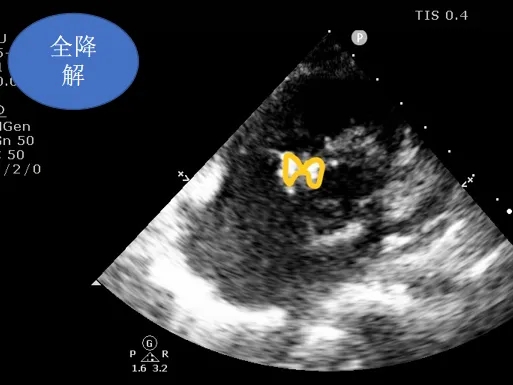

封堵器锁定后呈“蝴蝶状”明显盘状形态,室水平分流完全消失,主动脉瓣反流消失。

牵拉试验,封堵器稳定无移位,释放封堵器后超声下确认无残余分流,无主动脉瓣反流,三尖瓣反流同术前无增加。

大动脉短轴切面,封堵器释放后双盘紧贴间隔,呈现完美“工字形蝴蝶形”,顺应VSD形态及瓣膜形态。

MemoSorb全降解VSD封堵器展现了极佳的顺应性,在通过长隧道、小出口的VSD后,能顺利从“长哑铃”形态展开并固定为贴壁良好的“蝴蝶”形态。术后即刻超声评估显示,伞盘封堵完全,对相邻瓣膜无任何影响,主动脉瓣及三尖瓣均未出现反流。